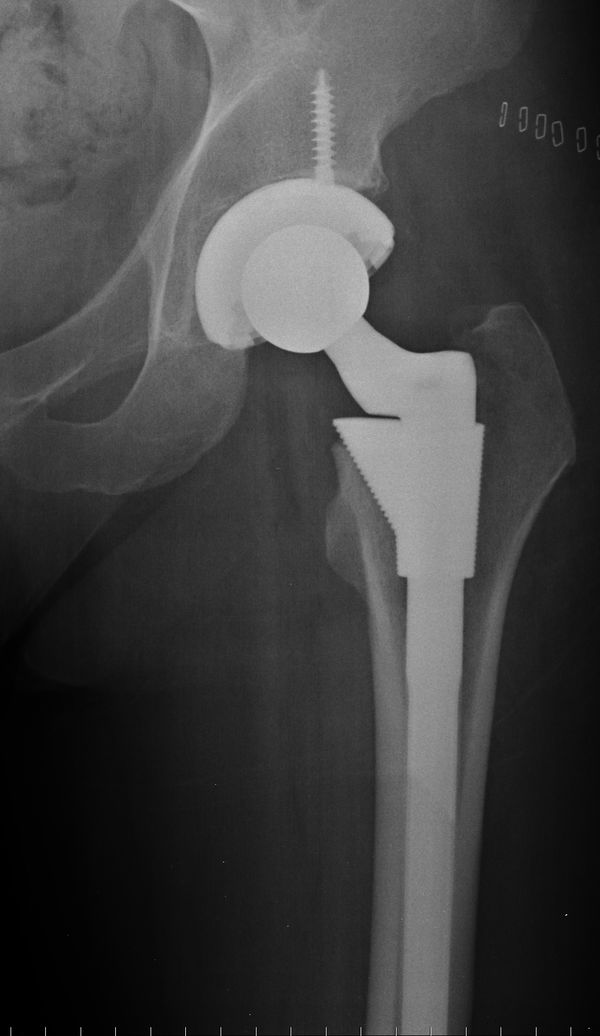

From www.phongtran.com.au

Anterior Hip Replacement Surgery Melbourne Titanium Hip Replacement Side Effects In the months after her debridement and prosthesis revision, the patient continued. One potential complication linked with hip replacement surgery is titanium toxicity. Worsens with walking, even with a cane or. Titanium is a common material used in hip implant devices and can result in. But while reactions to surgical hardware and implants are rare, they do sometimes occur. Hip. Titanium Hip Replacement Side Effects.